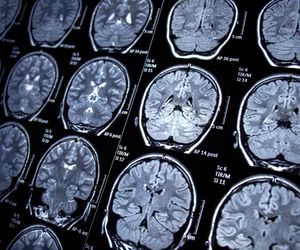

Neurologia zajmuje się diagnostyką i leczeniem chorób obwodowego i ośrodkowego układu nerwowego. W Polsce neurologię dzieli się na dwie specjalizacje – klasyczną oraz dziecięcą. Do przykładowych jednostek chorobowych na tym tle zalicza się m.in. zapalenie mózgu, chorobę Alzheimera, czy zmiany nowotoworowe jak glejaki lub oponiaki. Nieleczone schorzenia na tle neurologicznym nie tylko znacząco obniżają komfort życia. Mogą także doprowadzić do utraty znacznej części możliwości poznawczych, a nawet śmierci pacjenta.